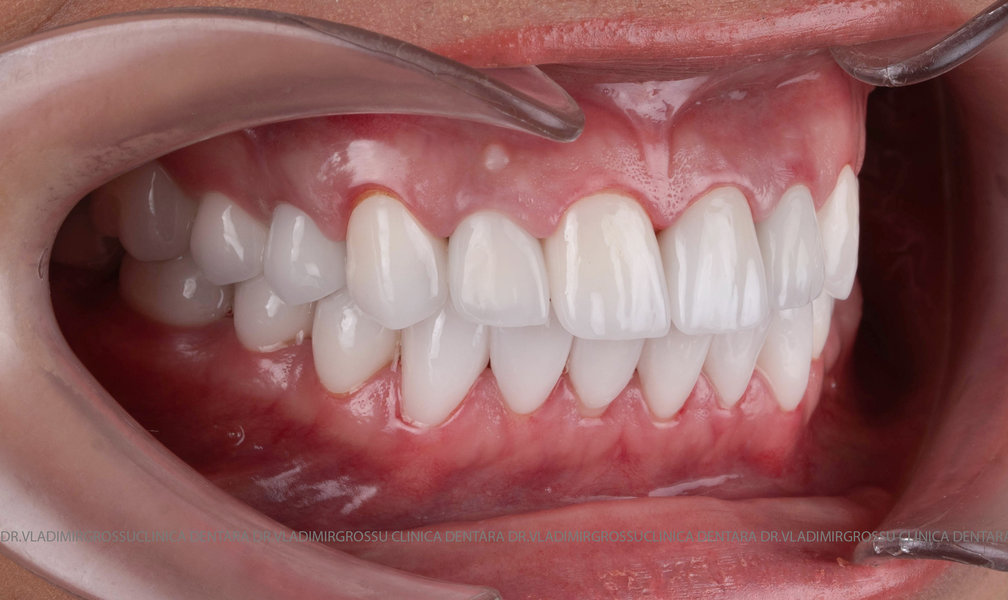

Cazuri clinice

Caz 2

Transformările estetice și impactul reabilitării asupra vieții pacienților

Reabilitarea dentară produce o schimbare vizibilă și profundă în aspectul pacientului, cu efecte pozitive evidente asupra stimei de sine și a calității vieții. Mulți pacienți relatează bucuria redobândirii funcției masticatorii și dispariția complexelor legate de aspectul dentar.

Designul noului zâmbet

În cazul în care pacientul pune la dispoziție fotografii vechi, acestea sunt analizate, însă adesea reabilitarea presupune crearea unui zâmbet nou, personalizat. Pacienții adesea au preferințe clare privind forma și aspectul dinților viitorului zâmbet, iar echipa medicală depune toate eforturile pentru a le respecta dorințele. Dacă este cazul, se propune un design alternativ, explicat pe larg pacientului, care, de regulă, îl acceptă. Protocolul foto-video este indispensabil pentru realizarea unor astfel de lucrări.